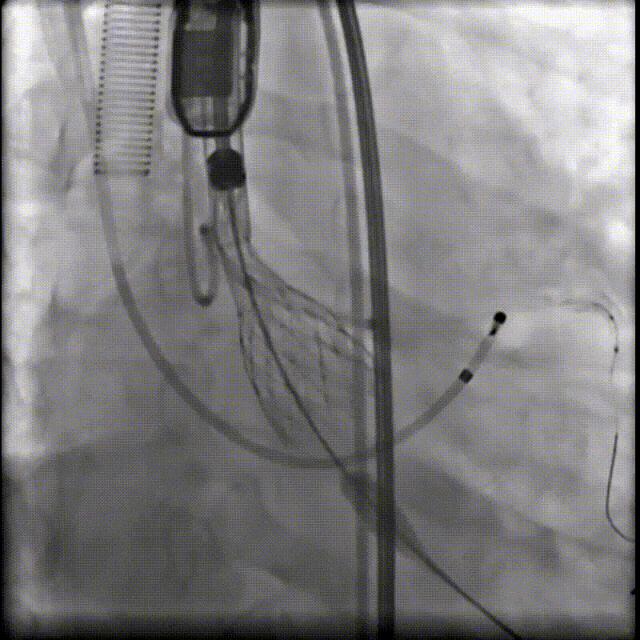

(1)Type 0二叶式主动脉瓣,瓣环适中,中度钙化,Type 0二叶瓣受瓣口形态及钙化影响,瓣架呈非理想椭圆形展开,对瓣架支撑力与顺应性提出了更高要求,同时该病例合并升主扩张,对同轴性和释放的稳定性提出了更高的要求。因此优先选择支撑性和顺应性兼具的瓣膜,以及较柔软花冠的瓣膜,降低对升主动脉的损伤,小锥角的设计进一步提升了瓣膜在释放的稳定性

(2)窦部空间较小,左侧瓣叶冗长,且开口位置在短轴平面,左冠冠脉风险较高,优先选择有收腰设计的瓣膜,降低冠脉风险并保留术后足够的VTC

综合病例解剖特点及患者年纪,决定使用第二代可回收的自膨瓣,可回收提高容错空间,为了降低冠脉阻挡风险,决定采用平衡收腰设计的TaurusElite 的瓣膜,先使用大鞘鞘芯进行预扩,然后上20F大鞘。

麻醉医师:患者本次因间断胸闷3年,再发伴加重2月就诊于我院,拟行经导管主动脉瓣置换术,麻醉选择气管插管全身麻醉,备体外循环,术中密切监测生命体征,维持血流动力学,考虑到冠脉风险,球囊预扩和瓣膜释放之后,严格监测血压和心率的变化。

超声医师:患者为重度主动脉瓣狭窄,术前超声充分评估,心腔大小,心腔容量是否充分,各瓣叶活动程度,该病例左侧冠脉风险较高,工作位以及最终释放超声下充分评估原生瓣叶到左冠侧瓣叶距离,进一步评估冠脉风险。